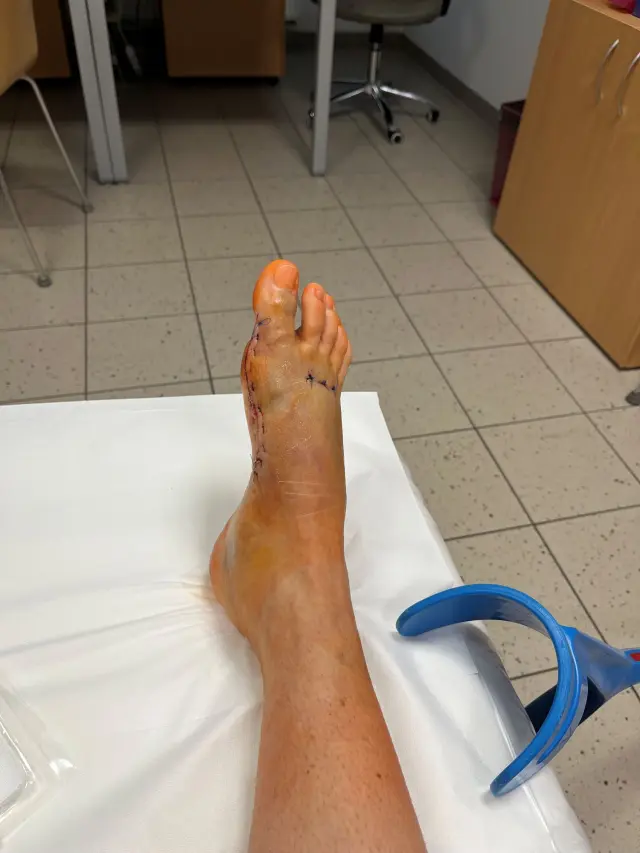

Další operace v prosinci

Moji milí a úžasní dárci. V prosinci mě čekají další dvě operace nohy, v pořadí to bude už šestá operace od roku 2021 a zdaleka ne poslední. Je to velká dřina, hodně to bolí, každá operace a narkóza si vezmou svoji daň. Ale vím, že jsou horší věci a neměnila bych, takže jedeme dál. Chtěla bych vám znovu všem strašně moc poděkovat. Opakuji se, ale Marťa, Andrejka, Donio a vy všichni, kdo jste mi přispěli a stojíte při mě, jste mi opravdu neskutečně pomohli a pomáháte ! Moc si toho vážím a jsem vám za to velmi vděčná.